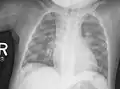

Au niveau du thorax, le chapelet costal est très évocateur. Il s'agit de nodosités saillantes et symétriques de la jonction entre les côtes osseuses et le cartilage costo-sternal (côtes et sternum). Elles sont alignées selon une ligne oblique en bas et en dehors, à partir de la ligne mamelonnaire (axe vertical passant par le mamelon). À ne pas confondre avec la saillie normale de l'extrémité antérieure des côtes, en dos d'âne asymétrique.

Les autres déformations thoraciques sont l'aplatissement antéro-postérieur, l'élargissement à la base, la projection du sternum en avant (thorax « en carène » ou « en bréchet de poulet » ou pectus carinatum), ou au contraire sternum enfoncé (pectus excavatum).

Au niveau du thorax, le chapelet costal clinique donne un aspect radiologique, surtout visible de profil, « en bouchon de champagne » des jonctions chondro-osseuses. En sus des déformations osseuses, on peut observer des atteintes pulmonaires par troubles de la ventilation.

Radiographie du thorax.